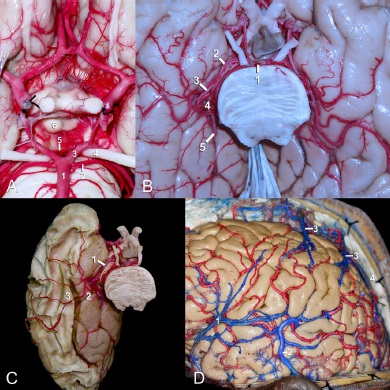

Figura 4 A. Arteria cerebral posterior: 1) arteria basilar, 2) arteria cerebelosa superior, 3) segmento P1 de la ACP, 4) nervio craneal oculomotor, 5) arteria talamoperforantes posteriores, 6) cuerpos mamilares. B. Cara ventral del lóbulo temporal y occipital y su relación con la arteria cerebral posterior: 1) arteria basilar, 2) segmento P2a, 3) segmento P2p, 4) segmento P3, 5) segmento P4. C. Disección de la región temporo-occipital por método Klingler e inyección vascular cerebral con látex. Irrigación de sustancia blanca y sustancia gris de la cara ventral de la región temporo-occipital: 1) arteria cerebral posterior, 2) giro parahipocampal, 3) fascículo longitudinal inferior. D: 1) vena cerebral media superficial, 2) vena anastómotica menor (Labbé), 3) venas corticales ascendentes, 4) seno sagital superior.

El trayecto de la ACP se divide en cuatro segmentos22 con sus respectivas ramas (Figura 4.B, C):

Drenaje venoso de la corteza occipitotemporal

La cara lateral del lóbulo temporal es drenada por las venas cerebrales medias superficial y profunda hacia el seno esfenoparietal o seno cavernoso, y por la vena anastomótica menor o de Labbé hacia el seno transverso. El drenaje de la cara lateral de la corteza parietooccipital se da mediante las venas corticales ascendentes hacia el seno sagital superior, mientras que el de la cara ventral de la región temporooccipital se produce a través de la vena basal de Rosenthal hacia la vena cerebral magna o de Galeno, y por las venas temporales hacia el tentorio24 (Figura 4D).